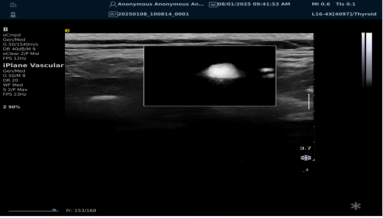

mFlowTM 超微血流显像技术

mFlowTM 超微血流技术在小型机器上率先实现微米级细小血管识别与低速血流捕捉,以往仅高端台式机具备此功能。该技术专注于颈动脉粥样硬化斑块内血流评估,无需造影剂,具有高分辨率、低运动伪像和高帧频成像特点。其优势如下:

image.png

? 运用 3D 壁滤波技术智能分析信号,可探测常规超声难以捕捉的低速血流,灵敏度高。

? 依据 Staub 标准对检查结果分级,直观展示斑块内新生血管血流,为斑块稳定性评估提供新指标。

? 基于多普勒原理,进行频谱测量并可进行VI指数测量,定量评估斑块内新生血管占比。

? 相较超声造影成像,无创便捷,为颈动脉易损斑块评估开辟新途径。